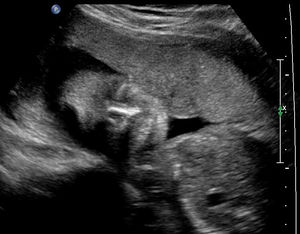

Ultrasound

Ultrasound imaging grew out of submarine technology! The threat of submarines during World War I and World War II led to a great deal of research into what became known as sonar. Sonar works by sending out pulses of sound and detecting the echoes when the sound is reflected back by objects. Bats use sonar to locate insects in the dark. In the 1940s and 1950s a number of engineers worked to adapt sonar to medical use; among the most influential were George Ludwig at MIT, John Julian Wild and John M. Reid in Minnesota, and Douglass Howry at the University of Colorado. In the early 1960s a number of products reached the commercial market, and doctors soon found many uses for ultrasound imaging, including gathering images during a pregnancy.